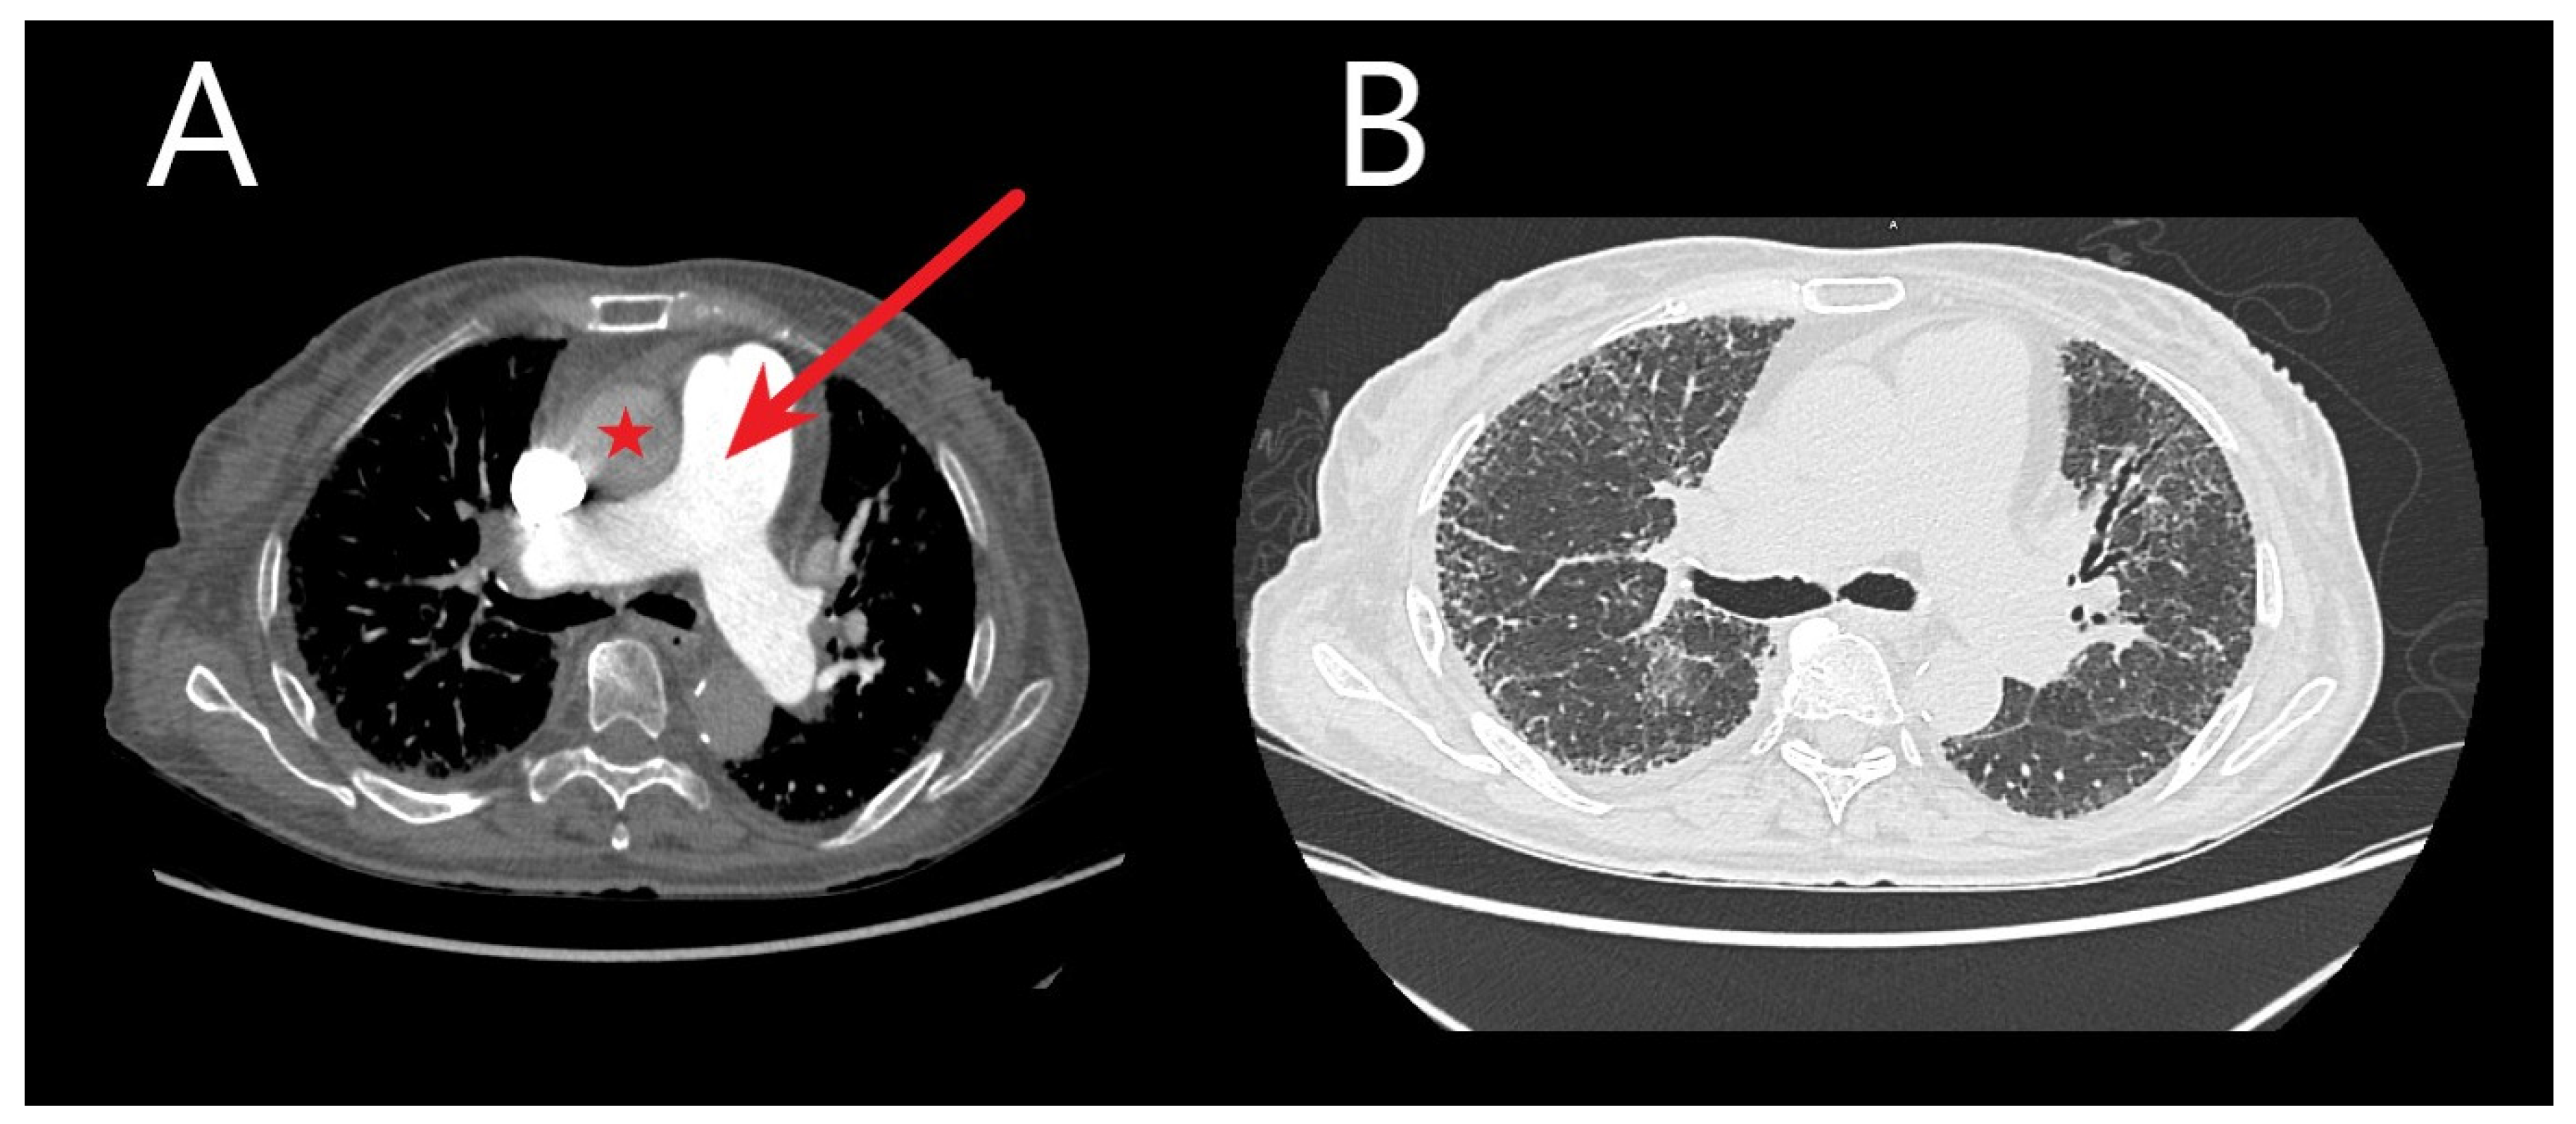

CT reveals cardiac changes reflective of chronic pressure overload in PH progression (Figure 1). These changes encompass right ventricular (RV) hypertrophy (wall thickness > 5 mm), dilated RV with an RV/left ventricle (LV) ratio > 1.0 in the axial plane, flattened interventricular septum, and dilated inferior vena cava [65]. Normally, the RV exhibits thin walls (4–5 mm), with less than one-third the thickness of the LV on chest CT. Increased RV:LV ratio and interventricular septal angle reflect RV enlargement and pressure overload in pre-capillary PH [61] but perhaps might be more accurately evaluated on gated cardiac MRI.

Figure 1.

Chest computed tomography (CT) images without and with contrast are shown from an idiopathic pulmonary fibrosis patient. (A) Transaxial images are shown demonstrating an enlarged main pulmonary artery (red arrow) compared to the ascending aorta (red star) at the same level—suggestive of pulmonary hypertension. (B) Transaxial images in the lung window demonstrate bilateral honeycombing, intralobular, and interstitial thickening.